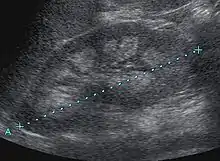

Nephrocalcinosis is diagnosed for the most part by imaging techniques. The imagings used are ultrasound (US), abdominal plain film and CT imaging.[9] Of the 3 techniques CT and US are the more preferred. Nephrocalcinosis is considered present if at least two radiologists make the diagnosis on US and/or CT. In some cases a renal biopsy is done instead if imaging is not enough to confirm nephrocalcinosis. Once the diagnosis is confirmed additional testing is needed to find the underlying cause because the underlying condition may require treatment for reasons independent of nephrocalcinosis.[9] These additional tests will measure serum, electrolytes, calcium, and phosphate, and the urine pH.[9] If no underlying cause can be found then urine collection should be done for 24 hours and measurements of the excretion of calcium, phosphate, oxalate, citrate, and creatinine are looked at.[9]